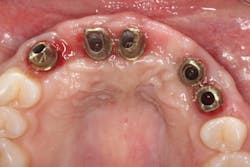

A 21-year-old female was injured five years ago in a jet ski accident. Seven of her maxillary teeth (Nos. 5–11) were avulsed along with the buccal plate. The patient was seen by several specialists to assess treatment options. Ultimately, she was allowed to heal over a few years (figure 1) and given a partial denture in the interim. The patient’s family had many consultations over the years to hear recommendations for restoring her smile with implant-retained crown-and-bridge treatment. At that point in time, options were expensive and the patient was too young to start treatment. The patient wanted fixed maxillary restorations to replace her missing teeth. Treatment began after the patient had graduated from high school and before entering college.

Figure 1: Full retracted view of full bite